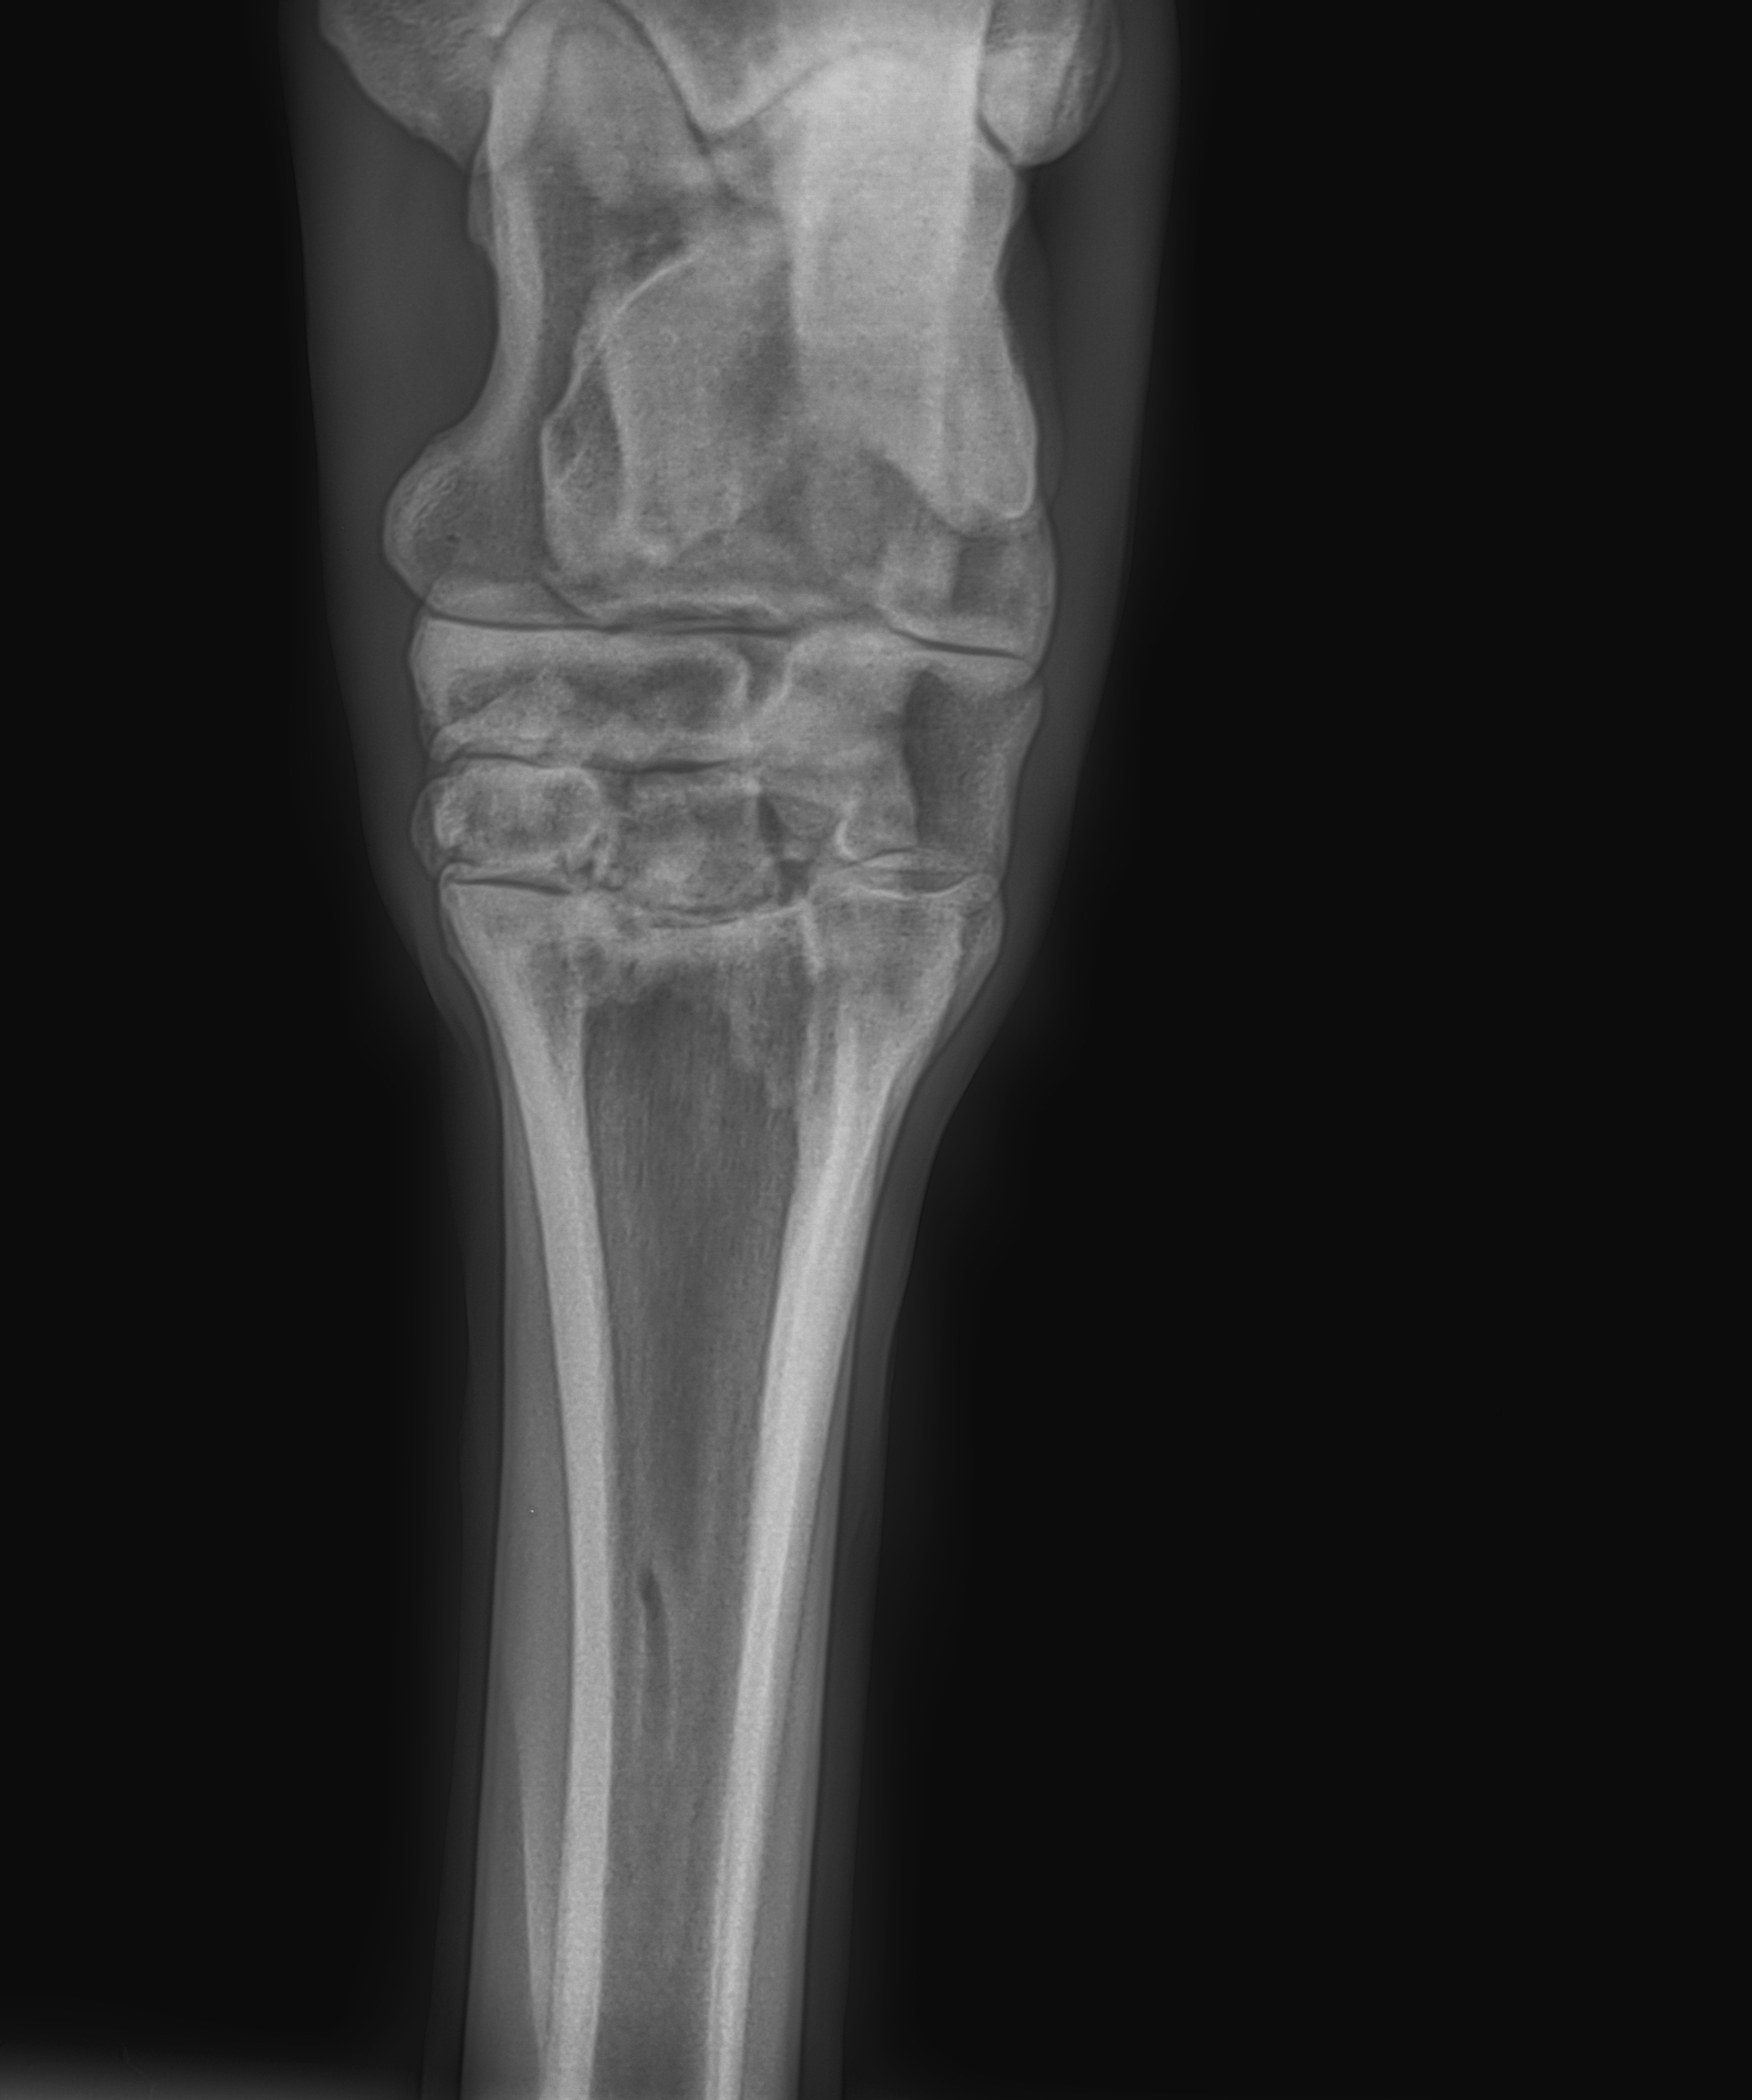

2013 márciusában cégünknél beüzemelésre került korunk egyik legmodernebb direkt digitális röntgenrendszere. A VetZ GmbH által kifejlesztett rendszer teljes mértékben vezeték nélküli, a központi egység mind a röntgengenerátorral, mind a digitális detektorpanellel vezeték nélkül kommunikál, megkönnyítve, meggyorsítva és egyben biztonságosabbá téve az eszközzel folytatott munkát. A kiváló minőségű, karbon- ill. alumíniumvázas, hatalmas érintőképernyővel és Dell gyártmányú célszámítógéppel ellátott készülék a Cuattro cég képalkotó szoftverét futtatja, mely elismerten a világ legjobbja jelenleg. Az elkészült röntgenképek kiváló minősége hatalmas segítséget ad az alapos diagnosztikai munkához, a rendszer képkészítési sebessége (5 másodperc/kép!) pedig a szavatossági vizsgálatok lebonyolítását teszi gyorssá és egyszerűen kivitelezhetővé.

A direkt digitális röntgentechnika előnye, hogy a képek néhány másodperc múlva már láthatók a monitoron, valamint az alkalmazott szoftver képes arra, hogy egy képen jelenítse meg egyszerre a lágyszövet és a csont röntgenképét is, így elképesztően jó minőségű és nagyon jól értékelhető képet lát szemünk a vizsgált területről.